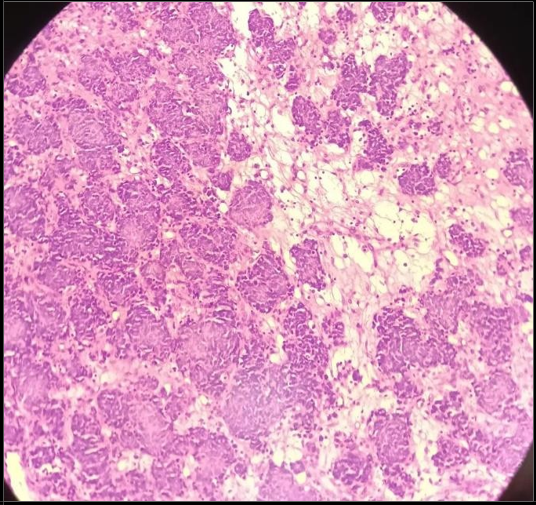

A biopsy of the lesion was subsequently performed. Histopathological examination revealed a malignant neoplasm. Immuno-histochemical staining demonstrated positivity for cytokeratin, synaptophysin, and CD56, with focal positivity for P63. Synaptophysin which is a reliable marker of neoplastic neuroendocrine cell and is normally found in synaptic vesicles of neurons and contains important role in diagnosing ganglio-neuromas, neuroblastomas, para-gangliomas, and small cell carcinomas, while Cytokeratin indicates the epithelial nature of the lesion. The tumor cells were negative for P40. The immune-profile was consistent with a diagnosis of olfactory neuroblastoma.

Figure 5: Showing morphological features of olfactory neuroblastoma exhibiting lobulated growth with nests and clusters of small round blue cells.

Figure 6: The tumor cells show hyperchromatic rounded nuclei with scanty cytoplasm.

Figure 7 and 8: Showing Immunohistochemistry of olfactory neuroblastoma .The tumor cells are positive for CD-56,synaptophysion(indicating neuroendocrine origin), calretinin and diffuse positivity for CKAE1/AE3 which indicates endothelial components of carcinoma.